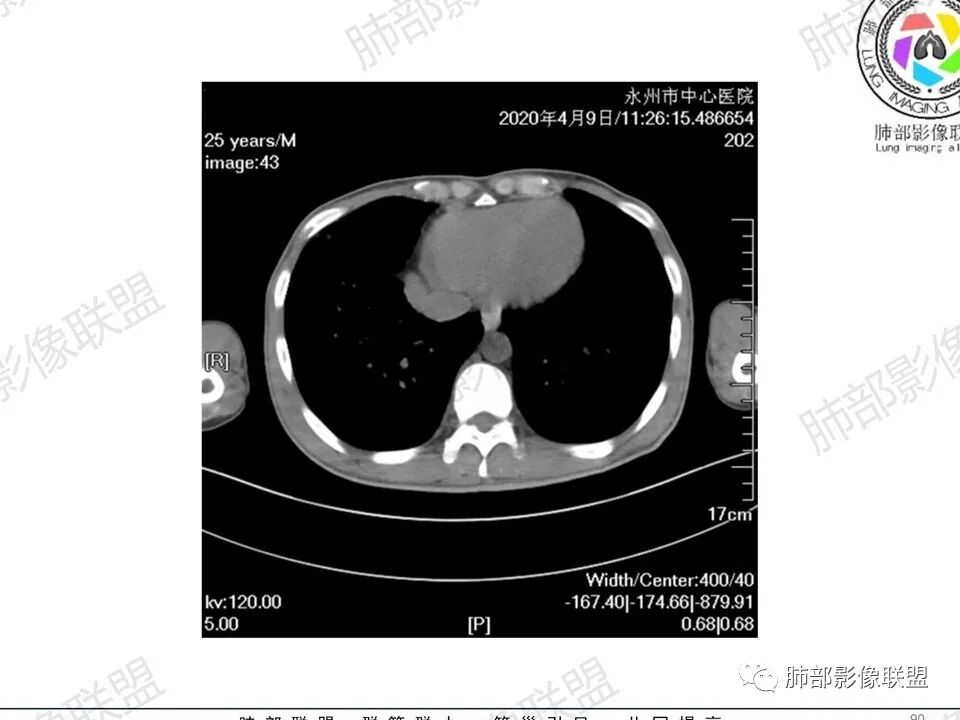

3、影像表现:双肺散在斑片影及结节影,部分结节内可见血管穿行,斑片影沿支气管血管束分布,近胸膜侧病变收缩不明显。部分中央淋巴间质增厚,小叶间隔增厚。病灶内支气管穿行,部分支气管略扩张。局部小结节呈串珠样改变。纵隔、肺门区、锁骨上及腋窝淋淋巴结肿大,部分有融合。心腔低密度。脾大。

6.心腔密度减低。提示可能存在贫血。

7.脾脏增大。

1.临床表现明显,纵隔及双肺门淋巴结显著肿大,临床最为担心的还是淋巴瘤!

尤其患者有贫血及脾脏增大,又有体表淋巴结增大时,这也是临床相对常见的情形。

淋巴瘤肺部浸润表现多样,多发结节影是其最常出现的影像学改变,尤其是霍奇金病。